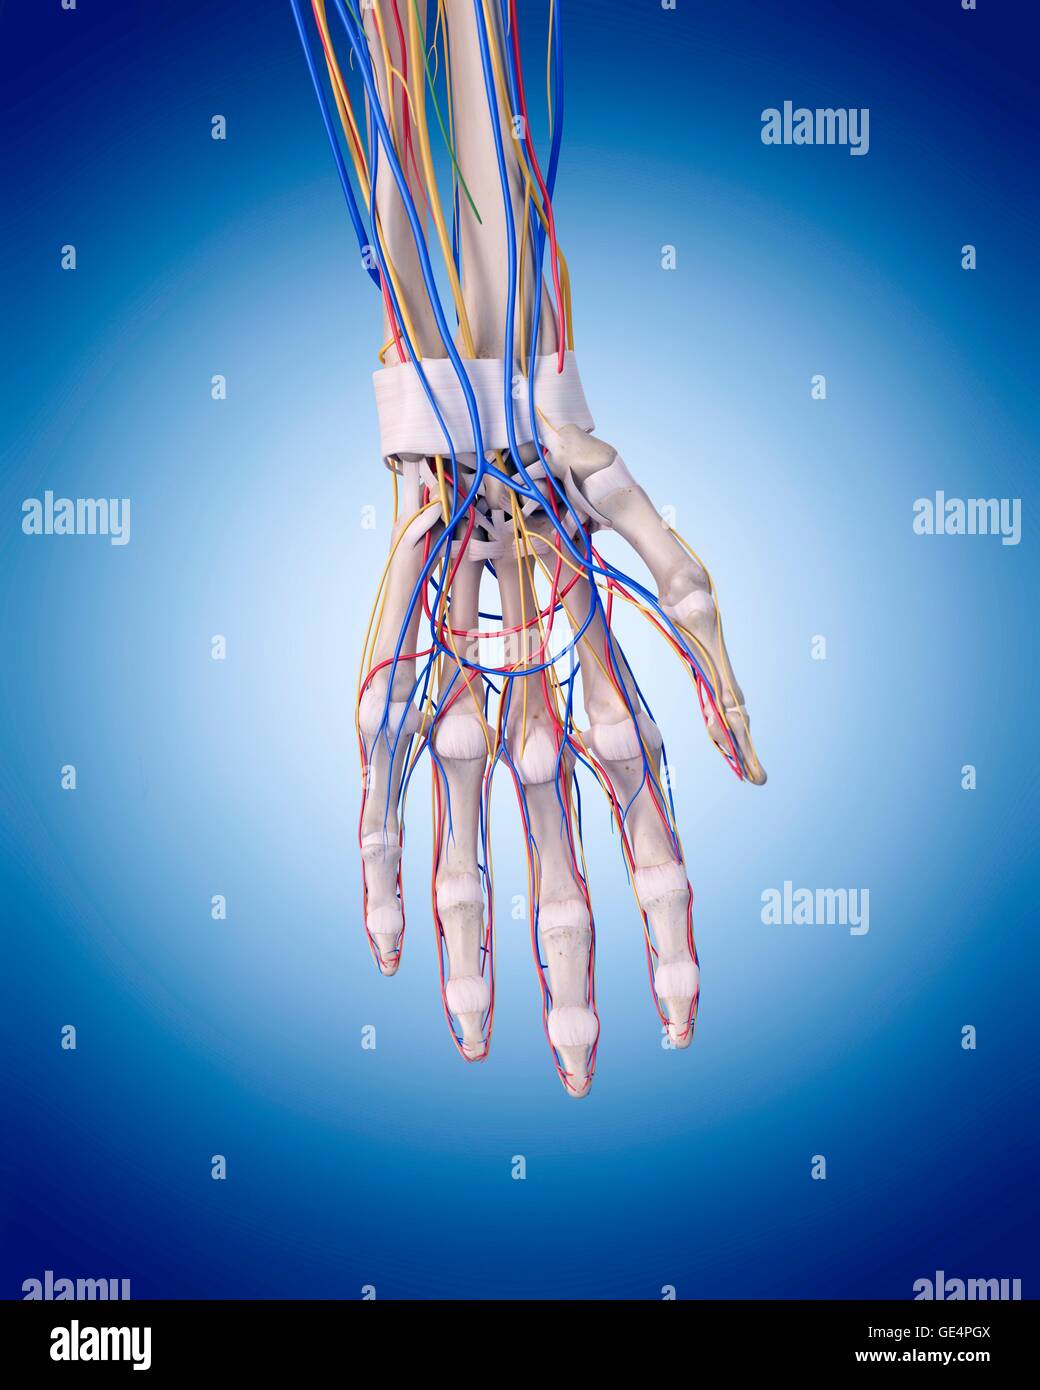

Venas de la mano. 3d fotografías e imágenes de alta resolución Alamy

Arterias y venas de la mano fotografías e imágenes de alta resolución Página 2 Alamy